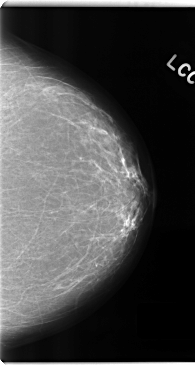

C_0192_1.LEFT_MLO

C_0192_1.LEFT_CC

LEFT_MLO LINES 4712 PIXELS_PER_LINE 2552 BITS_PER_PIXEL 12 RESOLUTION 50 NON_OVERLAY

LEFT_CC LINES 4744 PIXELS_PER_LINE 2528 BITS_PER_PIXEL 12 RESOLUTION 50 NON_OVERLAY